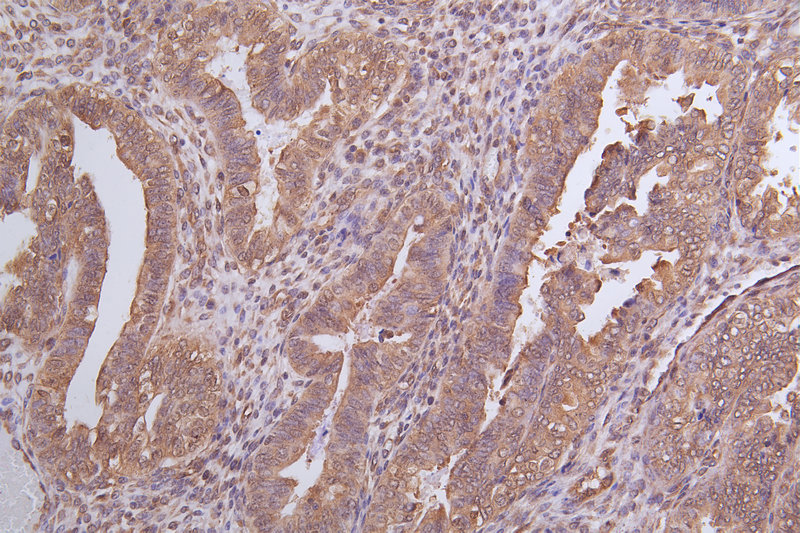

IHC image of CSB-RA824302A0HU diluted at 1:100 and staining in paraffin-embedded human endometrial cancer performed on a Leica BondTM system. After dewaxing and hydration, antigen retrieval was mediated by high pressure in a citrate buffer (pH 6.0). Section was blocked with 10% normal goat serum 30min at RT. Then primary antibody (1% BSA) was incubated at 4°C overnight. The primary is detected by a Goat anti-rabbit polymer IgG labeled by HRP and visualized using 0.05% DAB.